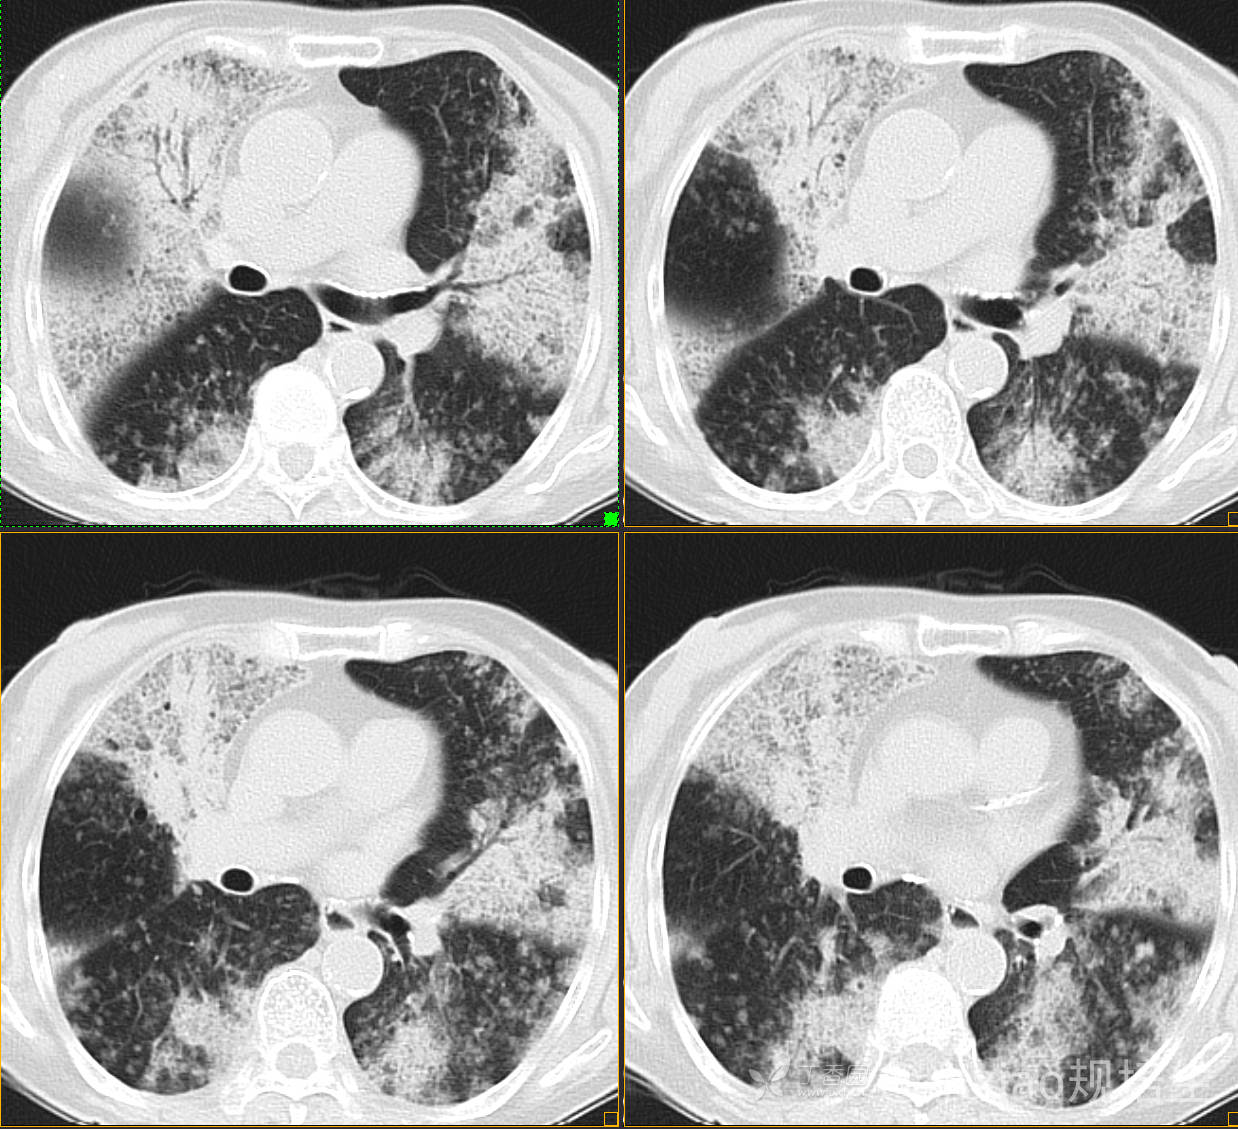

患者,女,89岁

咳嗽,咳痰一月余